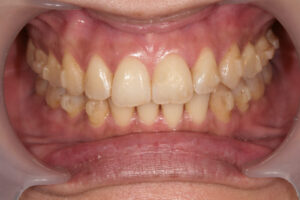

矯正したにも関わらず前歯が噛んでいない

Invisalign failure - Gum recession

Invisalign failure – Gum recession

歯肉が赤黒い

歯肉が削れて歯茎全体が萎んでしまった

移植など必要でしょうか

自分の歯で老後も過ごせること

1. 健康な歯茎  2.

歯茎を正常に戻して欲しいです